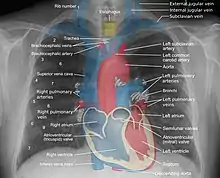

صورة إسقاطية ثلاثية الأبعاد للتصوير الإشعاعي الصدري، توضّح محتويات الصدر من الجوانب:الخلفي، الأمامي والجانبي.